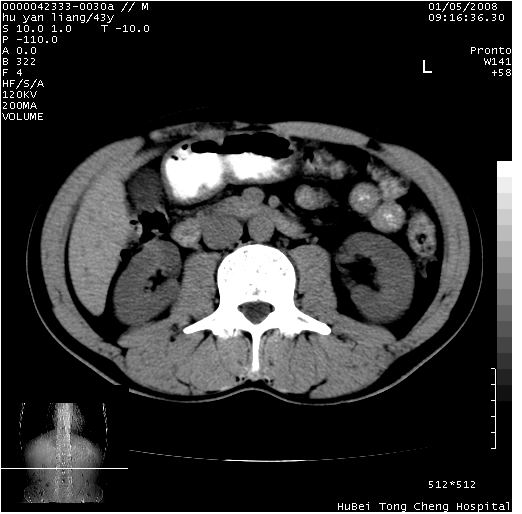

患者 男,43岁。右上腹不适1年余。既往有“肝右叶肝脓肿”病史,经保守治疗后痊愈。

b超提示:1)肝右叶肝内胆管结石。2)肝右叶占位性病变待排。

上中腹部ct轴位平扫+增强扫描(层厚10mm,螺距1.0,重建间隔10mm),图像如下:

肝右上叶偏后方较大团片状钙化灶,支持:肝脓肿后遗改变!

肝右叶后段团块状钙化灶,结合病史考虑肝脓肿痊愈后表现。